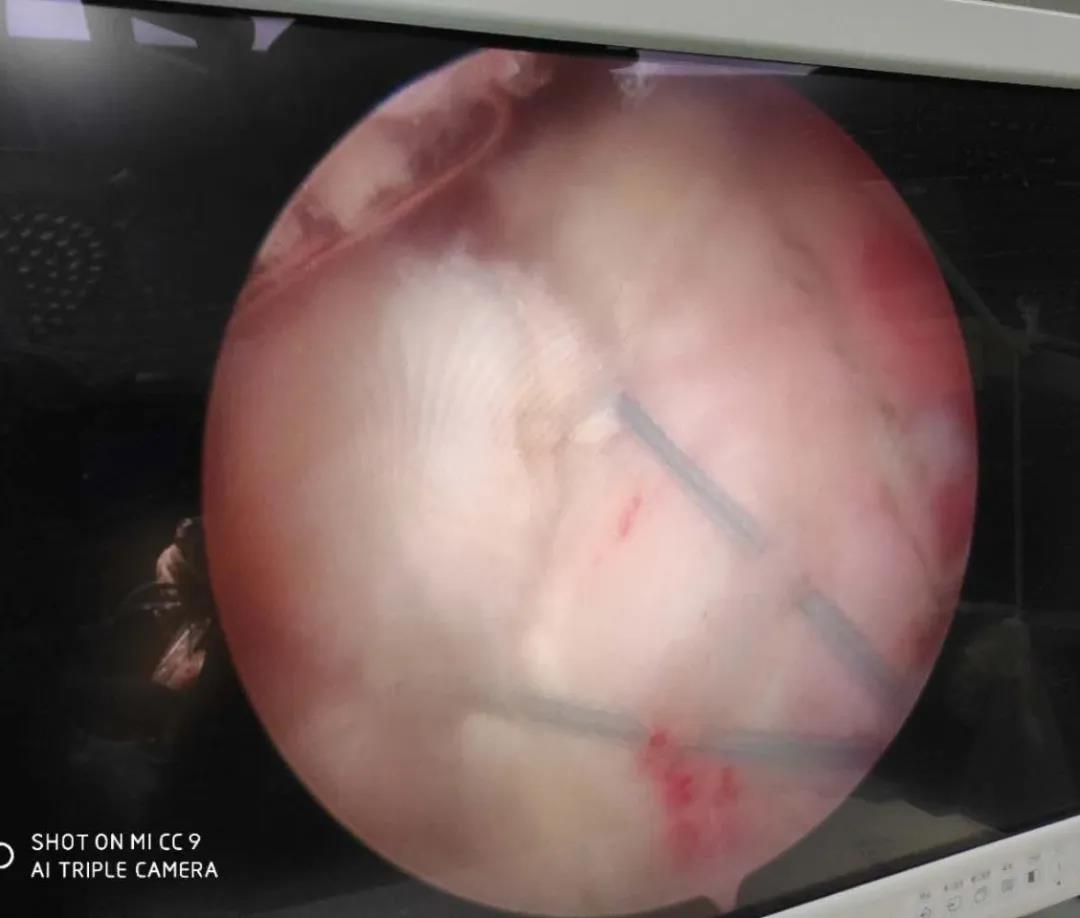

骨二科開展肩關節(jié)鏡下肩袖損傷修補術,采用雙排縫線橋技術,更好的促進肩袖撕裂的愈合,同時開展肩關節(jié)鏡下凍結肩(肩周炎)的松解治療,早期恢復肩關節(jié)的功能,減輕疼痛,同時開展肩關節(jié)Bankart損傷SLAP損傷及肩關節(jié)不穩(wěn)的關節(jié)鏡治療。

肩關節(jié)鏡下肩袖損傷修補術